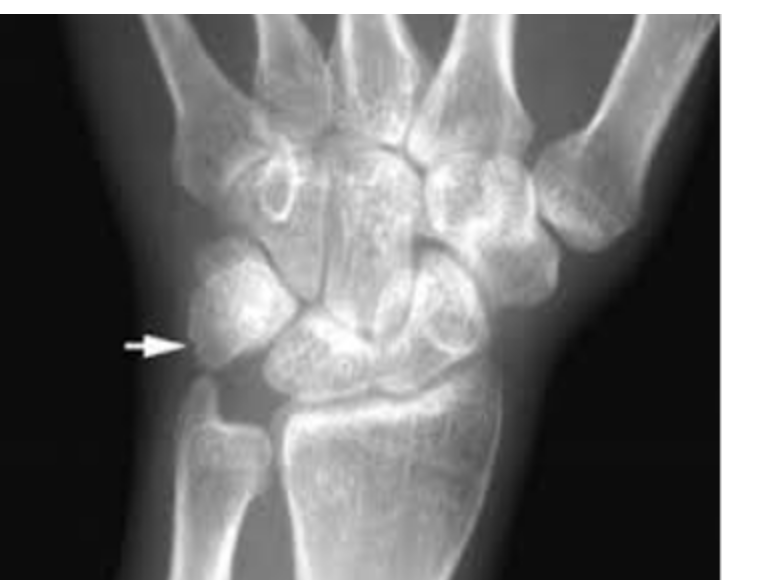

Which carpal bone is most commonly fractured? - falling on hand

scaphoid bone - which arti ulates with the radius -